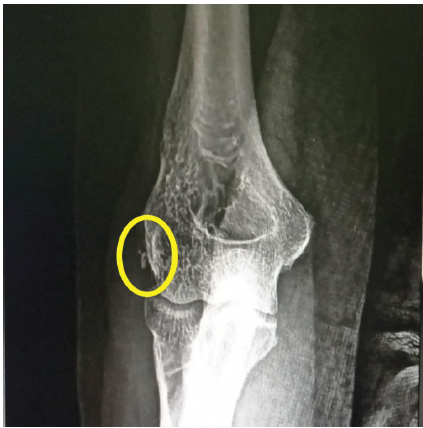

A 46-year-old right-handed female presented with severe left elbow pain for the past 1 year. The pain has progressively worsened, persisting even at rest and aggravating with movements of the forearm and wrist, such as lifting objects. There was no history of trauma or overuse of the elbow. A similar episode occurred one year ago, which was diagnosed clinically as lateral epicondylitis. Initially managed by oral naproxen 500 mg twice daily for 3 weeks, resulting in partial pain relief. This was followed by a structured physiotherapy program over 4 weeks, comprising progressive resistance exercises targeting wrist extensors, eccentric strengthening, and stretching of the extensor carpi radialis brevis. The patient reported moderate improvement in symptoms after completion of the program. However, 2 months later, pain recurred with increased intensity that was treated with a single dose of 1 ampoule of local triamcinolone acetonide injection around the lateral epicondyle. The patient experienced significant symptomatic relief within 1 week, with pain subsiding almost completely over the following fortnight. No further rehabilitation or physiotherapy was given after the injection. After 1 year, she presented with unrelenting pain for 2 weeks and rated 8 on the Visual Analog Scale (VAS), which was significantly hampering her daily activities. On physical examination of the left forearm, there was tenderness over the lateral epicondyle of the humerus and the proximal radioulnar joint. Pain exacerbated on wrist extension, and both cozen’s and varus stress tests were positive. There was restriction of flexion at the elbow joint (100°), and the Mayo elbow performance score was 60. A plain radiography of the left elbow revealed calcific deposits at the lateral epicondyle, suggestive of calcific tendinitis (Fig. 1). To evaluate soft-tissue involvement, MRI was performed, revealing proton density fat-suppressed hypointense thickening of the lateral collateral ligament (Fig. 2), further corroborating the radiographic findings.

Figure 1: X-ray image showing calcific deposits at the lateral epicondyle.